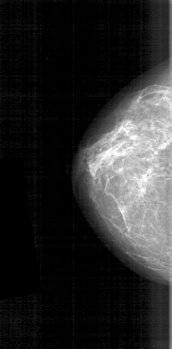

D_4119_1.LEFT_MLO

RIGHT_MLO LINES 5236 PIXELS_PER_LINE 2851 BITS_PER_PIXEL 12 RESOLUTION 43.5 NON_OVERLAY